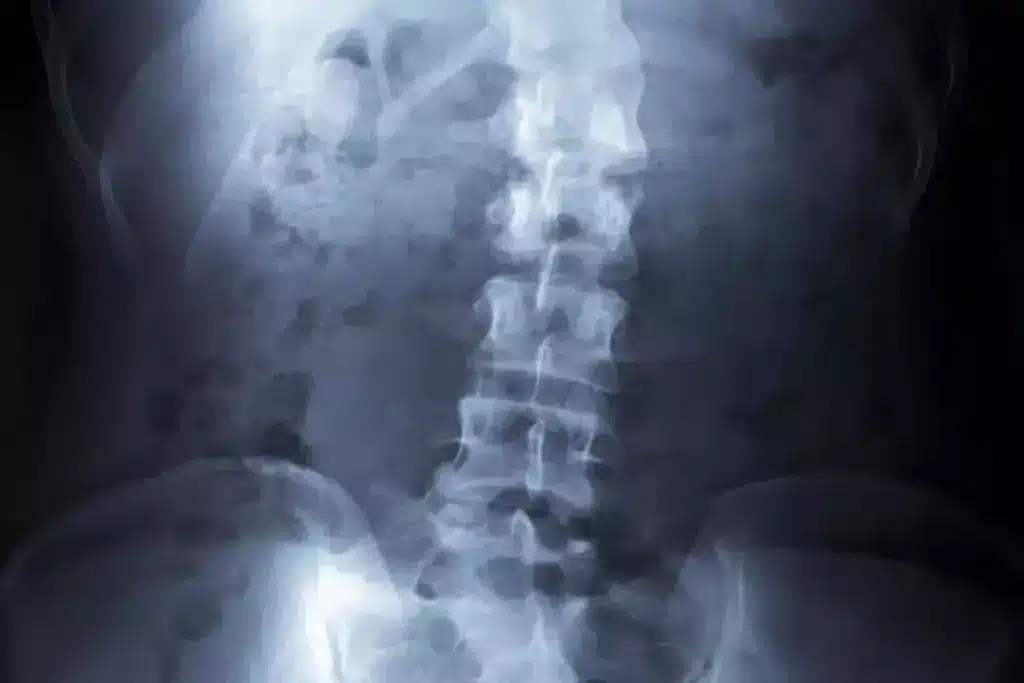

Measuring Severity: The Cobb Angle Explained

The Cobb angle is used to measure scoliosis severity from X-rays. It shows the degree of curvature. The higher the angle, the more severe the scoliosis. Treatment choices often depend on the Cobb angle, with more severe cases needing surgery.

For mild scoliosis, we often suggest watching and checking in regularly. These visits help us see if the curve is getting worse. We use X-rays to check the Cobb angle.

- Regular X-rays to assess the Cobb angle

How is the severity of scoliosis measured?

Doctors use X-rays to measure scoliosis severity. They look at the Cobb angle. A higher angle means a more severe curve.